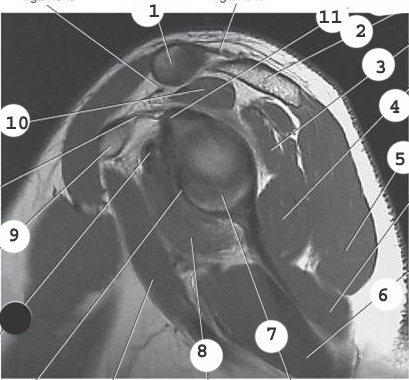

2

acromion

3

infraspinatus muscle

4

teres minor muscle

5

deltoid

8

subscapularis muscle

10

supraspinatus muscle